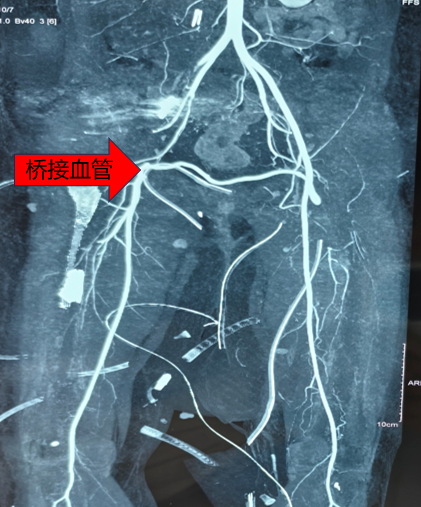

“既然无法直接吻合,我们就重建一条血液通路。”骨科樊俊俊副教授与手术团队经过多轮讨论后,决定采用“桥接血管移植技术”实施保肢。该技术核心在于取材患者自身功能相对次要的血管(如大隐静脉),作为“桥梁”,从健侧大腿引出一条血管跨越下腹部,为伤肢构建血液供应通道。

在手术显微镜高倍放大下,手术团队以极细缝线,将移植血管与健康动脉两端进行精准吻合。过程中不仅需要应对血管吻合的技术挑战,还需同步处理骨盆骨折及多处软组织撕裂伤,对团队的技术储备与团队协作提出严峻考验。

在毕龙副主任医师指导下,手术团队历经数小时精细操作,随着血管夹开放,鲜红血液经重建的“生命之桥”流入右下肢,足背动脉恢复搏动,成功保肢。术后,在ICU与护理团队的密切监护及康复指导下,杨女士右下肢血运逐步稳定,肤色与温度恢复正常,创面愈合良好。目前已开始早期功能锻炼,生活质量获得显著改善。